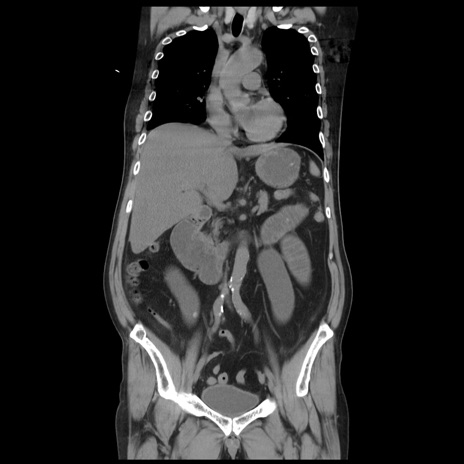

症例20(冠状断像)

【症例】 60歳代男性

【主訴】 腹部膨満、嘔吐

【現病歴】5日前頃より倦怠感を認め食事量減少し4日前の朝嘔吐、食事摂取困難となった。 3日前近医受診し点滴施行され整腸剤などを処方された。 当日他院を受診し、腹部膨満著明、炎症反応の上昇(CRP10.8、WBC11200)あり、紹介受診となる。

【身体所見】 意識JCS1 受け答えがはっきりしないBP 111/57mHg、 P 67bpm、、BT35.2°C、SpO2 97%(RA)、 腹部:膨隆、打診で鼓音あり、全体的に圧痛有り、腸蠕動音(-)、反跳痛ははっきりせず。

【データ】WBC 11400、CRP 14.20